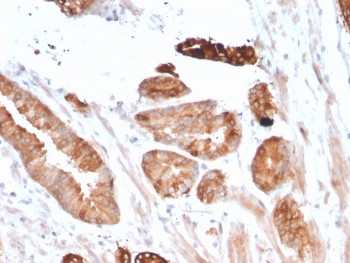

Product information "Anti-CD135 / FLT3, clone FLT3/2458"

1 mg/ml in 1X PBS, BSA free, sodium azide free. Stem cell tyrosine kinase (STK-1) has been cloned from a CD34+ hematopoietic stem cell enriched library and identified as the human homolog of a previously identified gene of Mouse origin designated either Flk-2 or Flt-3. The STK-1 cDNA encodes a protein of 993 amino acids with 85% identity to Flt-3/Flk-2. STK-1 is a member of the type III receptor tyrosine kinase family that includes Kit (steel factor receptor), Fms and PDGF. STK-1 expression in blood and marrow is restricted to CD34+ cells, a population greatly enriched for hematopoietic stem/progenitor cells. STK-1 antiserum recognizes two polypeptides in these cells. The Mouse homolog of STK-1, designated Flt-3/Flk-2, is expressed at high levels in hematopoietic cells and also in neural, gonadal, hepatic and placental tissues. It has been suggested that STK-1 and its murine homolog Flt-3/Flk-2 may function as growth factor receptors on hematopoietic stem and/or progenitor cells. Protein function: Tyrosine-protein kinase that acts as a cell-surface receptor for the cytokine FLT3LG and regulates differentiation, proliferation and survival of hematopoietic progenitor cells and of dendritic cells. Promotes phosphorylation of SHC1 and AKT1, and activation of the downstream effector MTOR. Promotes activation of RAS signaling and phosphorylation of downstream kinases, including MAPK1/ERK2 and/or MAPK3/ERK1. Promotes phosphorylation of FES, FER, PTPN6/SHP, PTPN11/SHP-2, PLCG1, and STAT5A and/or STAT5B. Activation of wild-type FLT3 causes only marginal activation of STAT5A or STAT5B. Mutations that cause constitutive kinase activity promote cell proliferation and resistance to apoptosis via the activation of multiple signaling pathways. [The UniProt Consortium]

| Application: | IHC (paraffin) |